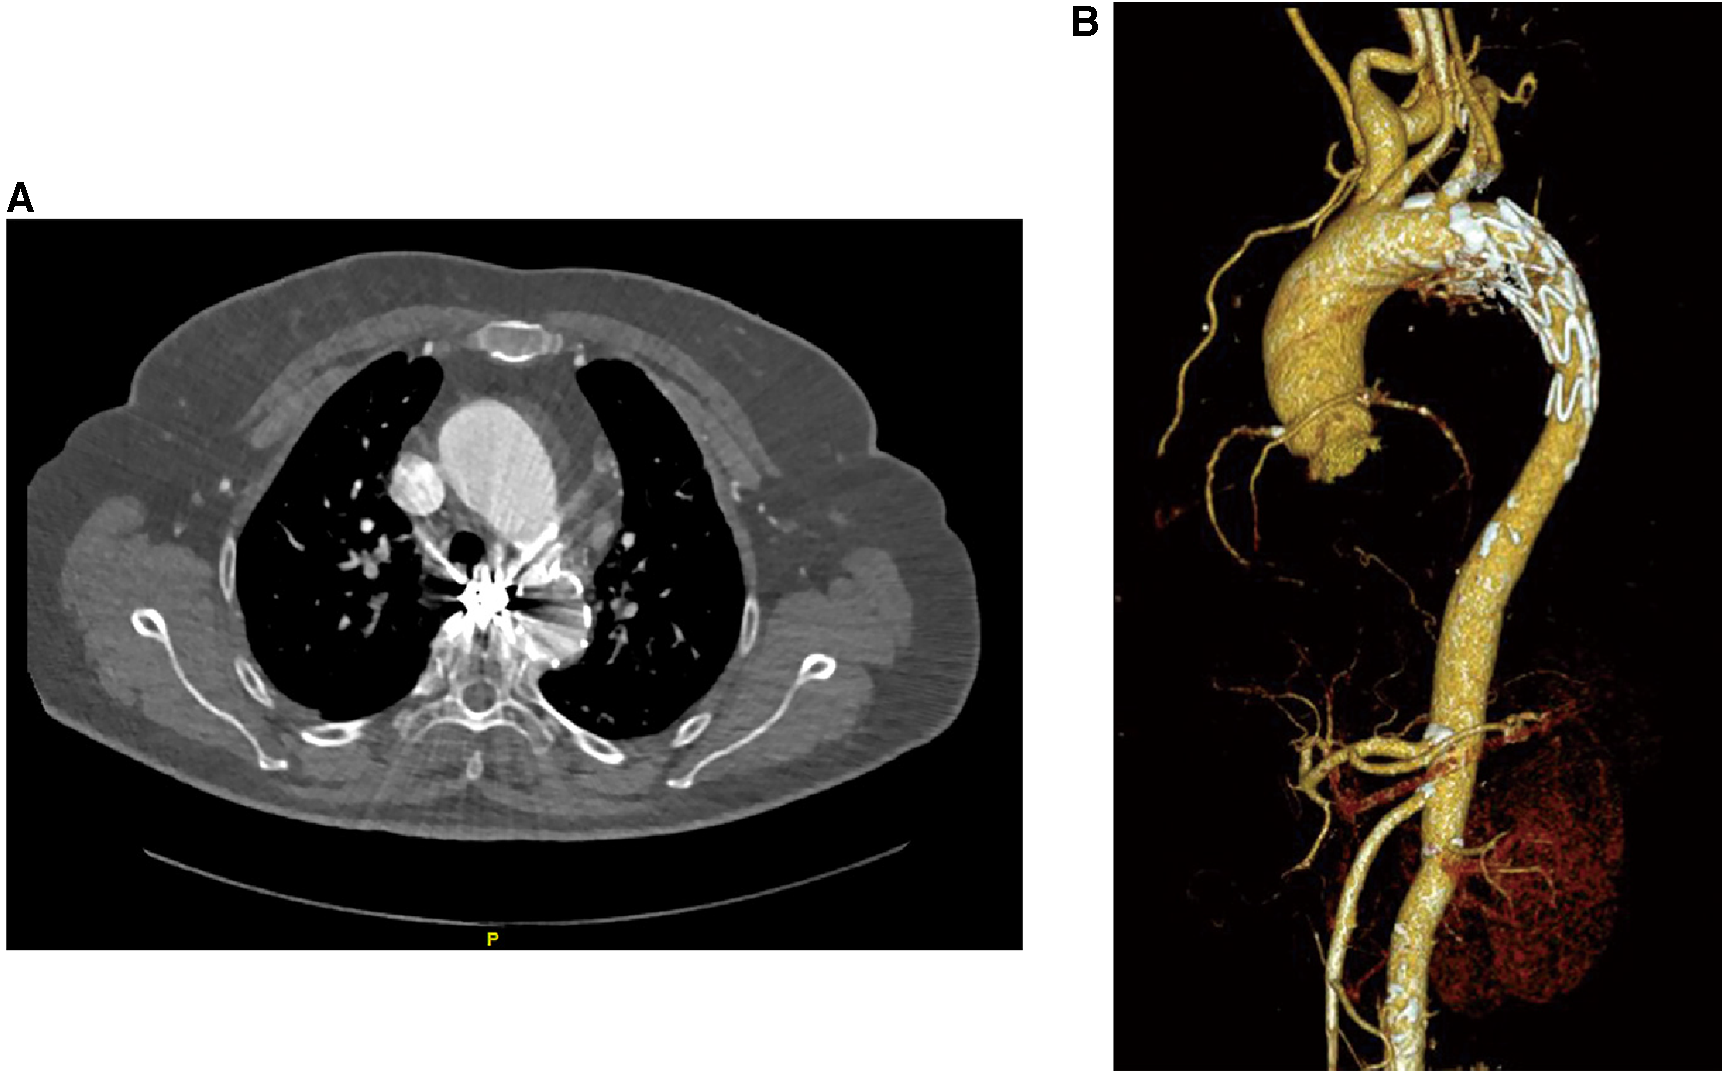

The patient was discharged from the hospital without any complications. Follow-up after 1 year, utilizing CT angiography and three-dimensional aorta reconstruction, revealed an absence of contrast filling in the BAA, indicating a positive prognosis during the 1-year follow-up (Figure 3). Despite the patient's reluctance to undergo further hospital-based examinations due to financial constraints, an ongoing assessment was sustained through telephone interviews conducted every year to evaluate the patient's clinical status until the fourth year. Throughout the series of telephone follow-ups, the patient consistently expressed satisfaction with the treatment outcomes and claimed no discomfort.

Figure 3

Patient's follow-up examination pictures after 1 year of treatment. (A) CT angiography was performed on the patient 1 year after treatment, and the scan suggests the presence of metallic artifacts from coils within the BAA. (B) Three-dimensional reconstruction of the vessel based on the CT angiography data shows no rupture of the BAA and no new collateral arteries supplying the BAA.